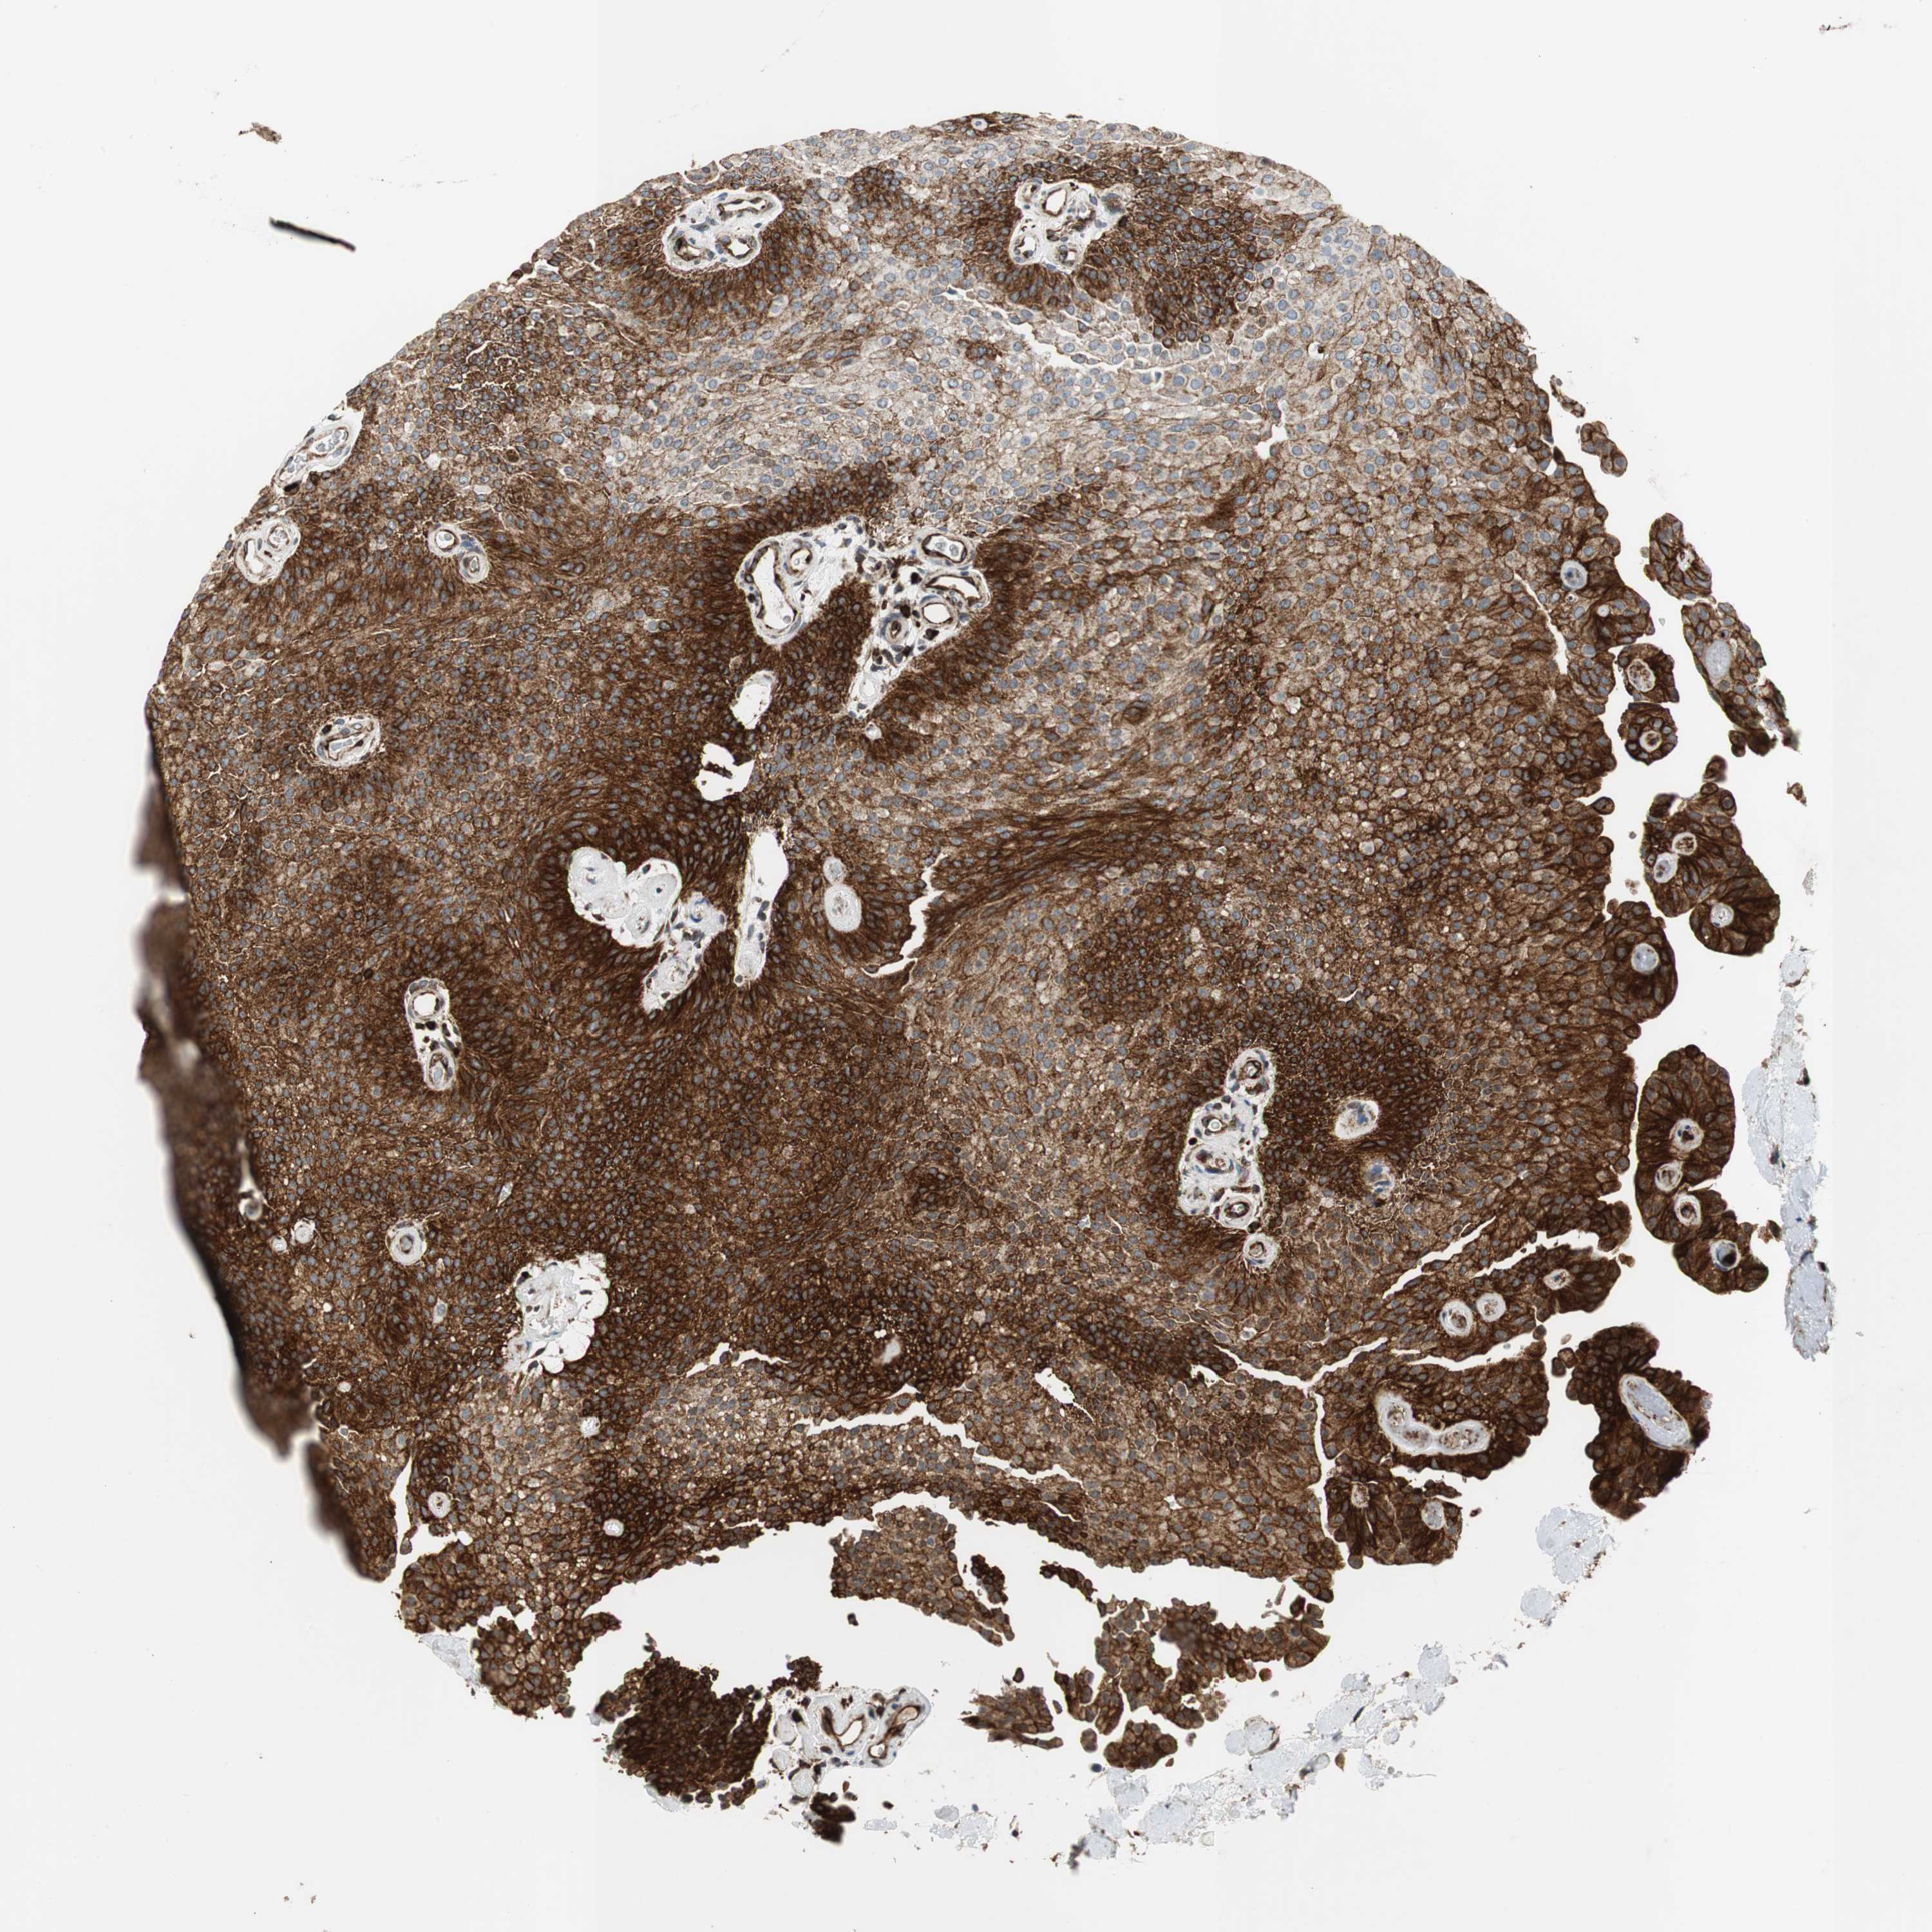

UROTHELIAL CANCER - Protein expressioni

A mouse-over function shows sample information and annotation data. Click on an image to view it in a full screen mode. Samples can be filtered based on level of antibody staining by selecting one or several of the following categories: high, medium, low and not detected. The assay and annotation is described here.

Note that samples used for immunohistochemistry by the Human Protein Atlas do not correspond to samples in the TCGA dataset.

Antibody stainingi

Antibody staining in the annotated cell types in the current human tissue is reported as not detected, low, medium, or high, based on conventional immunohistochemistry profiling in selected tissues. This score is based on the combination of the staining intensity and fraction of stained cells.

Each image is clickable and will lead to virtual microscopy that enables deeper exploration of all samples and also displays staining intensity scores, fraction scores and subcellular localization as well as patient and tissue information for each sample.

HPA039247

HPA043684

HPA063394

CAB004621

CAB005887

Staining

High

Medium

Low

Not detected

Intensity

Strong

Moderate

Weak

Negative

Quantity

>75%

75%-25%

<25%

None

Location

Nuclear

Cytoplasmic/membranous

Cytoplasmic/membranous,nuclear

Urothelial carcinoma, High grade

Urothelial carcinoma, Low grade